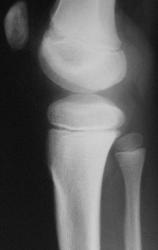

Мальчик 10 лет. Травма 1 год назал ( сомнительная).  4 мес. назад обнаружили плотное образование в обл. бугристости бб. кости. За это время увеличелось на 13. При пальпации очень плотное, без болезненное, не подвижное. Ваше мнение? Нужна ли активная хирургическая тактика?

С учётом клиники, можно предположить, что речь идёт болезни Осгуд-Шляттера, хотя привычной картины для этой болезни не видно на снимке. А, что за метод представлен на 3 слева снимке?

Я однажды наблюдала рост костно-хрящевого экзостоза из бугристости большеберцовой кости. Возможно, здесь тоже самое.

Если на на снимке не визуализируется,  но при этом образование как вы пишите плотное и имеет место быть атрофии кортикала от давления, можно предположить о хондроме.

А ведь "тенюху" то видно она на широком основании,  ещё возможно хрящевой экзостоз.

Возможно, на структурном снимке и будет видна тень. Хорошо видна нечеткость контура кортикального слоя по переднему контуру б/берцовой кости в области проксимального метафиза.

А мне что-то не кажется это нормальным вариантом ростковой зоны, и надколенник здесь как бы отодвинут от бедра (в прямой проекции его вовсе не видно). А что думают об этом наши любимые детские рентгенологи?

А ведь Петрович ПРАВ! Надколенник смещен кпереди и весьма неравномерно - верхние отделы надколенника смещены кпереди больше, по сравнению с нижними. По всей видимости, что-то "невидимое" отодвигает надколенник кпереди. А что у нас "невидимое" - может "бяка", состоящая из хрящевой ткани?

Прооперировали. Заключение гистологии - ХОНДРОМА.

Огромное спасибо Вам коллега за представленный результат. Случай можно считать законченным.

Коллега, а не могли бы Вы полностью процитировать протокол (описание) морфологогического исследования, а не только заключение? Предполагаю, что обнаружены хондроциты и митозы. А еще что-то есть?

ПРИСОЕДИНЯЮСЬ! Хотелось бы уточниь локализацию ХОНДРОМЫ.